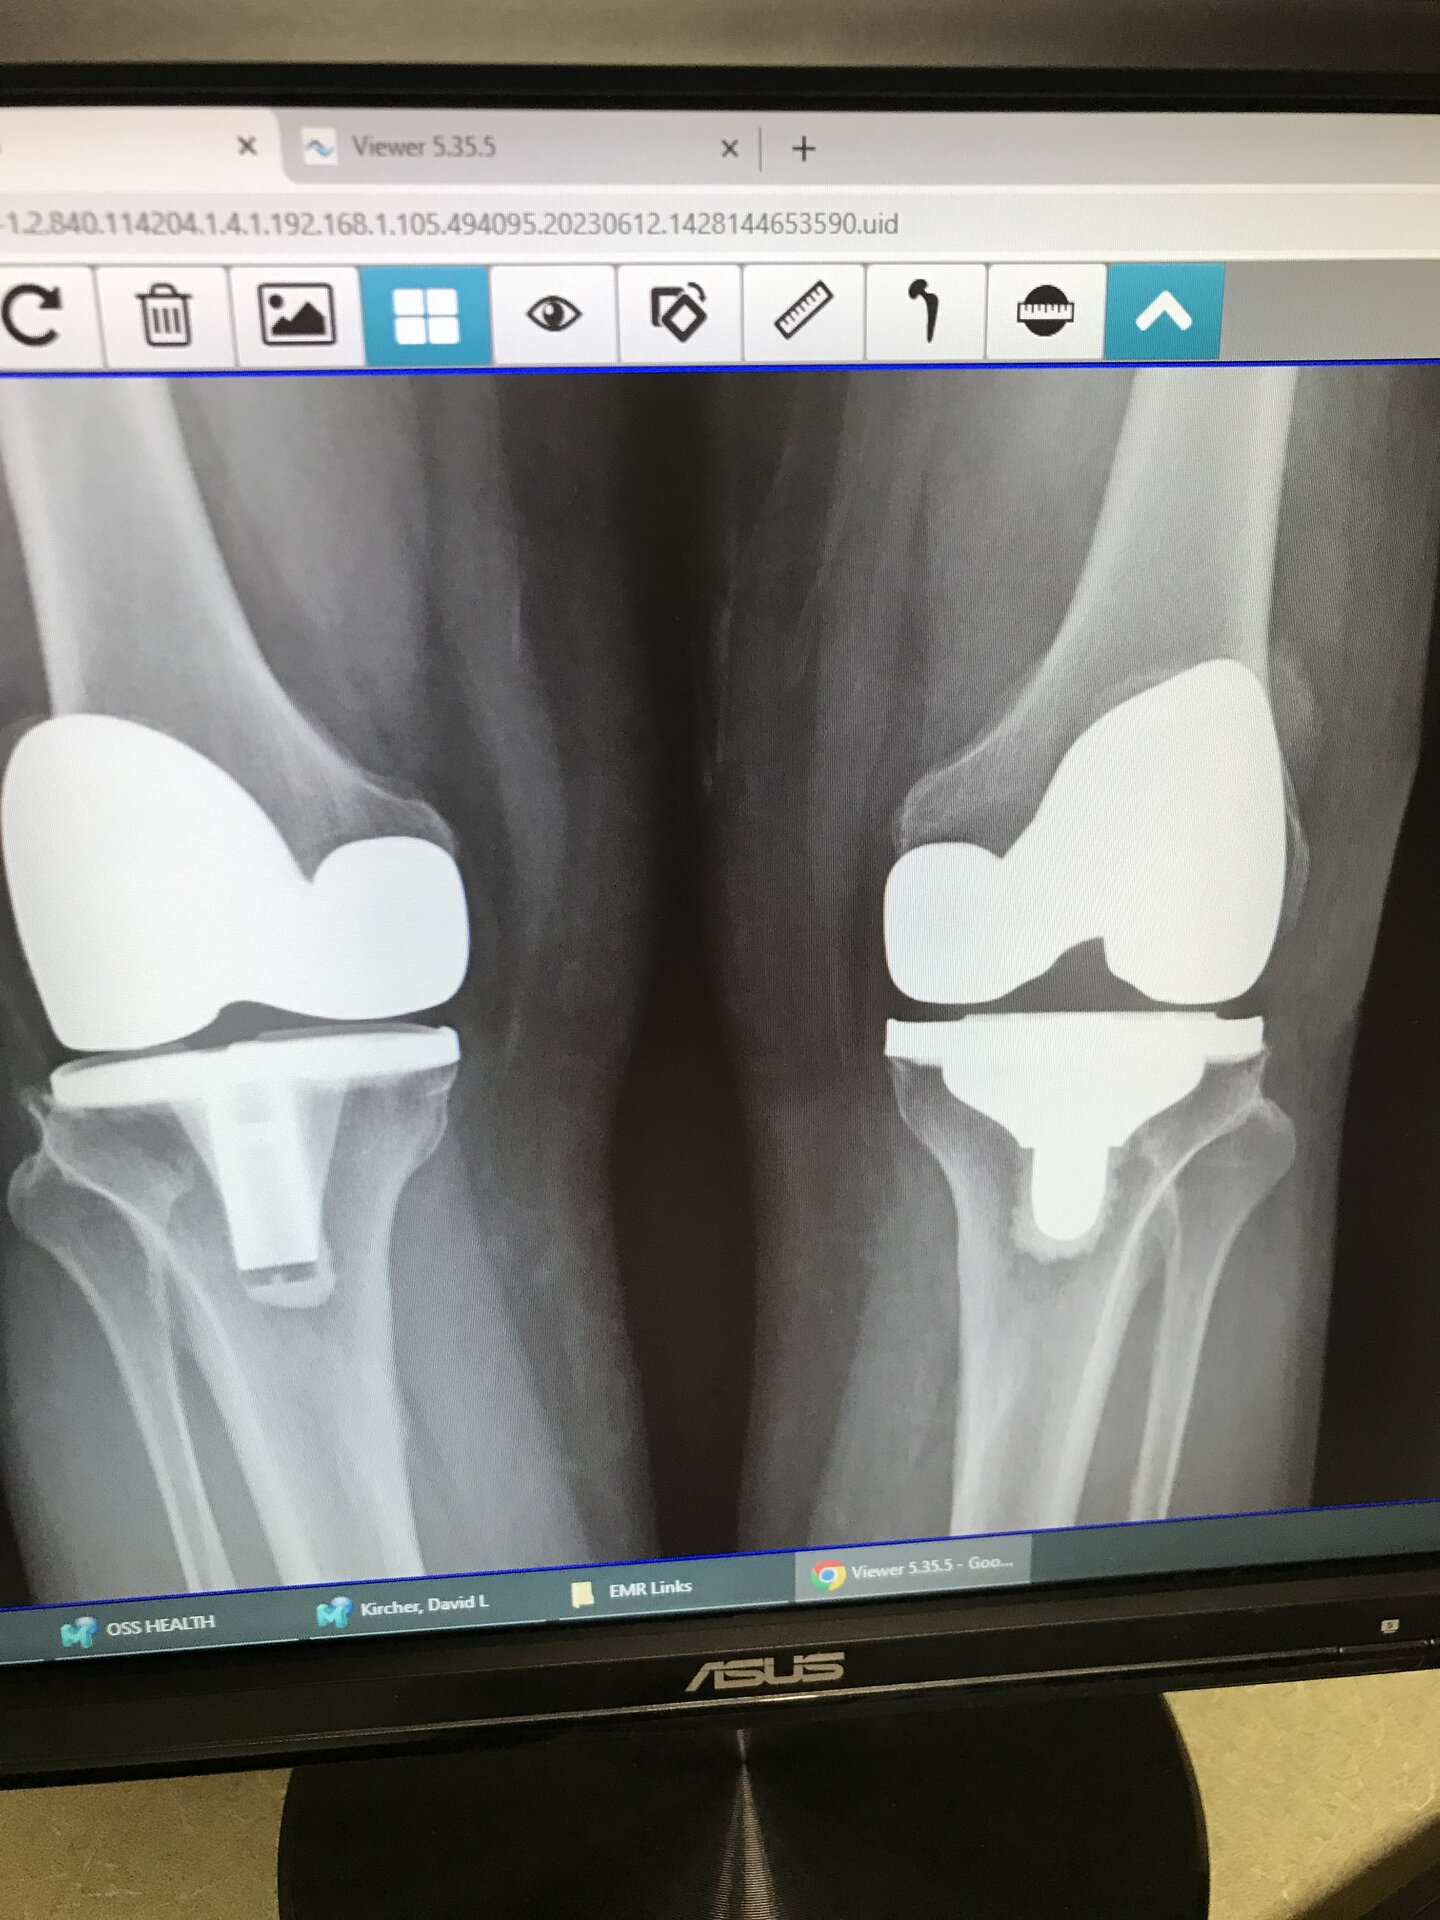

X-Rays of my knees. The one on the right is my left knee. It was done 2 years ago next month. The one on the left is my right knee that was replaced 18-20 years ago. I’d have to look it up to be sure but it’s been a long time ago. If you look and the bones and the implants you can see the difference. 5F8BE522-AB93-4666-BF4F-4B7486F4DF81.jpeg 95B54618-C230-4ECC-98AE-A43C746D1CE0.jpeg